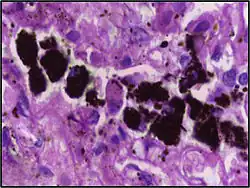

Comparison of pigmented pulmonary macrophages

| Disease | Macrophage name | Macrophage pigment appearance (HE stain) | Usual macrophage location | Associated medical history | Image | Image comment |

|---|---|---|---|---|---|---|

| Chronic pulmonary congestion | Siderophages | Brown-golden and refractile.[5] | Alveoli[6] |

|

![]() |

Siderophage (black arrow), and interstitium with edema, hemosiderin deposition (black arrow) and collagenous thickening, indicating heart failure. |